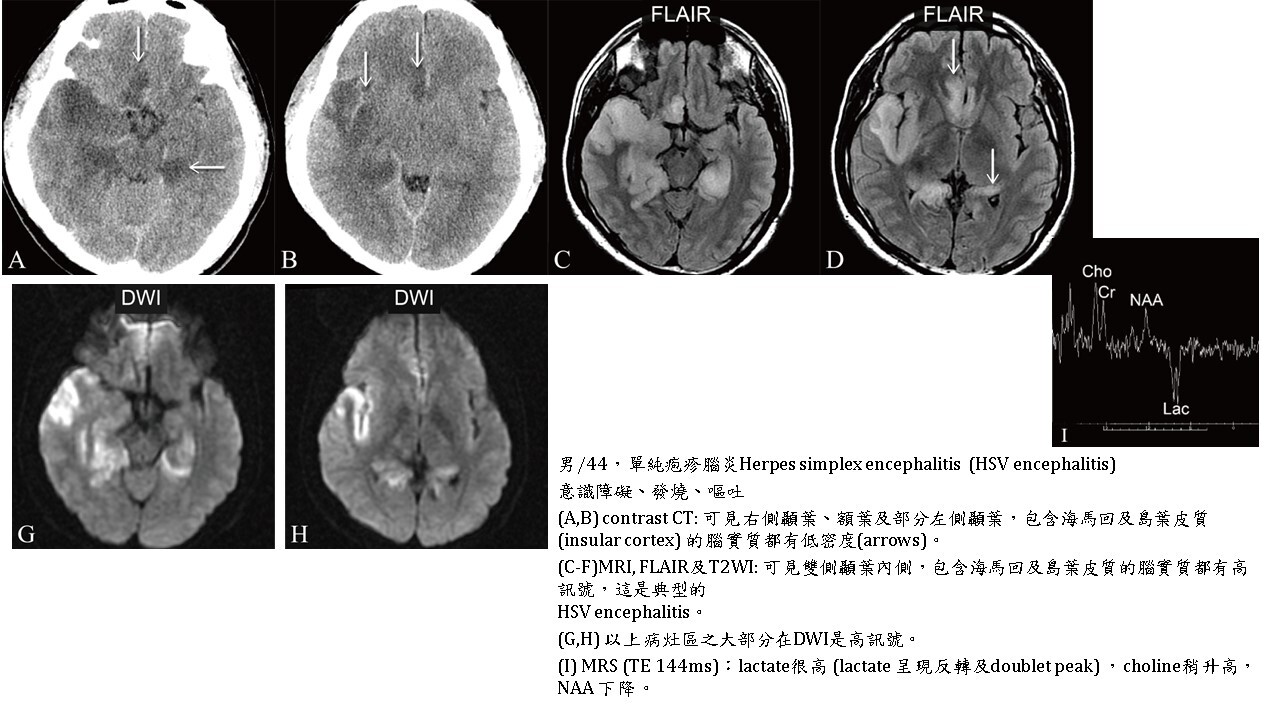

Encephalitis, 部分區域DWI 會hyperintense。

DWI最主要用於腦梗塞急性期時,腦組織細胞性水腫(cytotoxic edema),使腦組織之水分子布朗運動(Brownian motion of water molecules)受到妨礙,即水分子的擴散受到抑制 (diffusion restriction),在DWI下訊號很高,變得很白